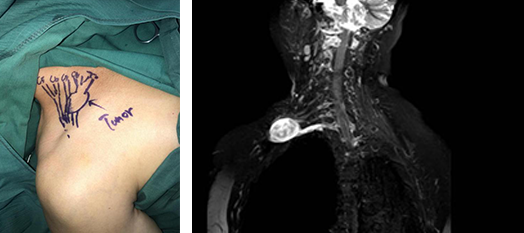

2019年12月27日,陈主任接诊后,为刘老太安排了检查,影像扫描见肿物与臂丛神经相连,周围神经组织受压明显。陈主任手术团队考虑到肿物位置较深,手术效果不好将引起上肢瘫痪,手术难度大,风险性很大,因此术前要仔细检查,术中在显微镜下仔细分离肿瘤,尽可能把手术风险降到最低。

完善各项检查后,考虑肿物性质为神经鞘瘤,陈步国、董自强、唐兆麟手术团队为老太进行了“臂丛神经探查肿物切除术”,术中于刘老太右侧锁骨上1厘米自胸锁骨突肌内缘至斜方肌前缘做长约5厘米横行切口,切开皮肤,分离皮下软组织,向深部分离颈阔肌显露颈外静脉。于颈7、颈8神经下方触及一肿物。因为肿物较大,且在臂丛神经周围,位置较深,经过一个小时的仔细分离,避开了神经将肿物细心成功分离,而神经主干完整保留。术后麻醉解除后,患者上肢的活动功能较术前没有变化。